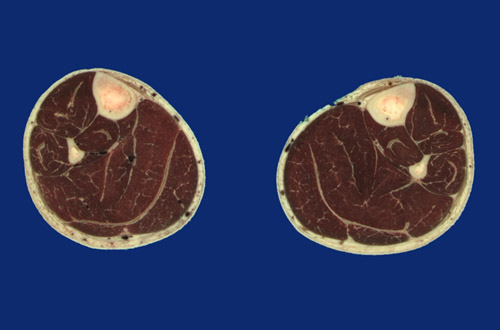

Identify the following regions in the image above: Tibia - Fibula - Posterior tibial artery & vein - Tibialis anterior - Interosseous membrane - Tibialis posterior - Flexor digitorum longus - Gastrocnemius, medial head - Gastrocnemius, lateral head - Soleus - Flexor hallucis longus - Peroneus longus - Peroneus brevis - Extensor digitorum longus